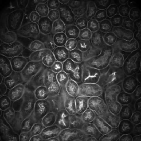

For visual evaluation we provide the segmentation results of the proposed method using two different datasets: and , sampled at different depths within the volumes. The first row shows original microscopy images , , and from and the second row displays the segmentation results corresponding to the first row. To better visualize the segmentation results, we highlighted individual tubules with different colors and overlaid them onto the original microscopy images. Similarly, the third row exhibits original microscopy images , , and from . Their corresponding segmentation results are shown in the fourth row. Note that the model which was trained on was used for during the inference stage. Although the shape, size, and orientation of tubular structures presented in are all different from , the proposed method can still successfully segment and identify individual tubules presented in as well as individual tubules in .